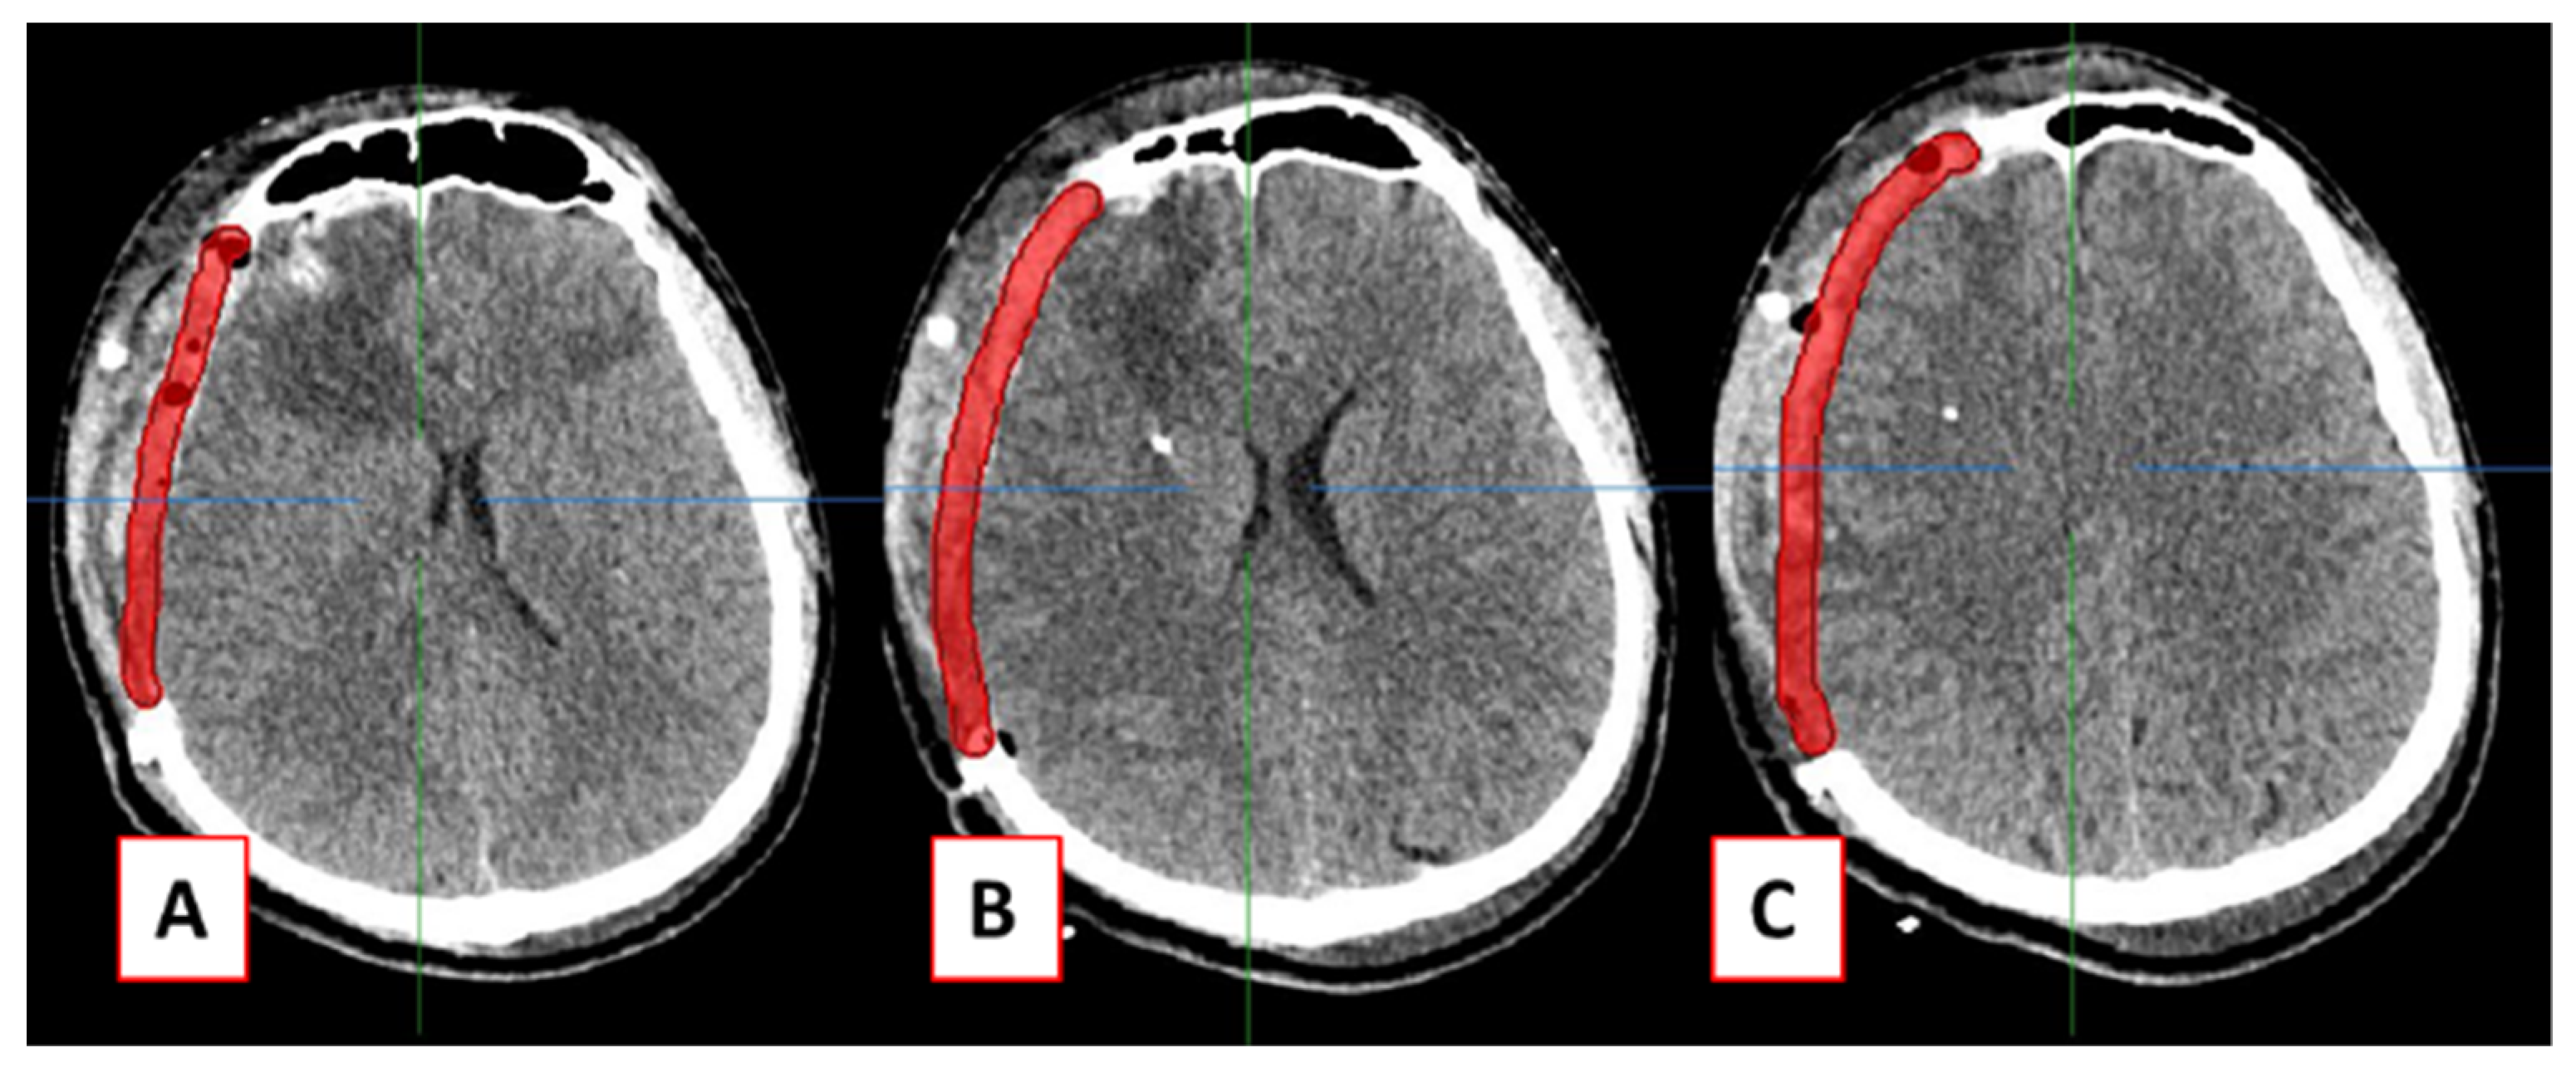

2.1. Design of Cranial Implants Using 3-Matic Software

2.2. Design of Cranial Implants Using MITK Software